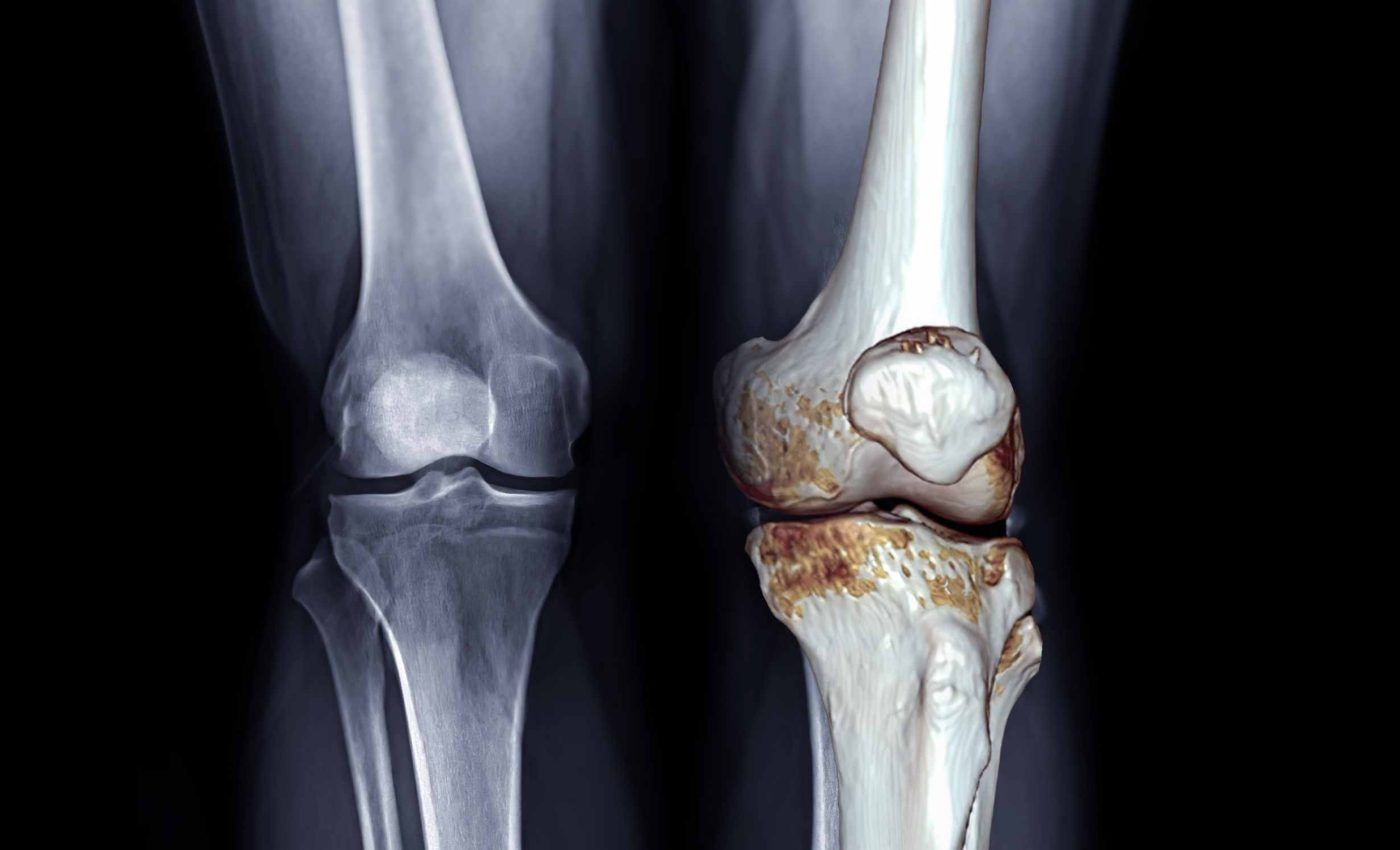

Artroza afectează peste 528 de milioane de persoane, iar aproximativ 365 de milioane suferă de forme localizate la genunchi, potrivit estimărilor globale. Boala duce la deteriorarea progresivă a cartilajului, rigiditate și limitarea mobilității, iar pentru mulți pacienți recomandarea standard rămâne administrarea de antiinflamatoare.

Scorurile privind durerea, rigiditatea și capacitatea funcțională au fost comparate, rezultatul fiind unul clar: metodele mecanice și fizice, care reduc încărcarea pe articulație și întăresc musculatura, oferă cele mai bune rezultate.